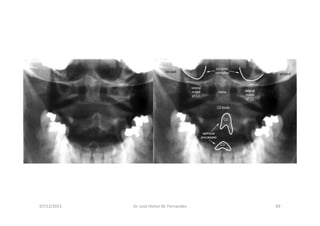

RX com a boca aberta mostrando atlas e axis

07/12/2015 Dr. José Heitor M. Fernandes 40

Upper Cervical Spine –

No subluxation

Skull to atlas subluxation

ATLAS SUBLUXATION

figura

07/12/2015 Dr. José Heitor M. Fernandes 41